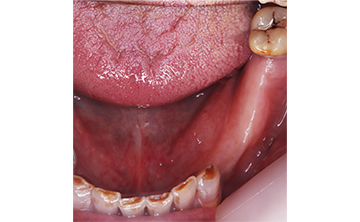

虫歯を放置して10年くらいの症例です。お口の中には、上あごは、一本しか歯が残っておらず、全く噛めないということで来院された患者さんです。痛い時期はどのようにして過ごされたのかと聞くと、とにかく痛み止めとお酒で痛みをごまかして過ごされたそうです。

すごい良く我慢されましたねとお伝えして、今後は、痛い時は安心してご来院くださいと伝えたら、ホッとされていました。小さい頃のトラウマで、とにかく歯科医院に行くことが怖かったそうです。

10年間虫歯を放置すると虫歯というより、歯が無くて噛めないので、咀嚼という問題が発生します。食べ物をお口の中へ入れても噛めないので、そのまま丸のみという食事になってしまうと胃や腸への負担は必須となり、癌や他の疾患へかかりやすますね。